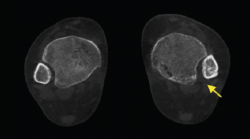

Figura 9. Se aprecia un desplazamiento lateral de los sesamoideos en deformidad del hallux valgus.

- Valoración rotacional del primer radio y desplazamiento de los sesamoideos. Valoración de la deformidad y rotación del primer radio, así como el desplazamiento lateral de los sesamoideos (Figura 9).